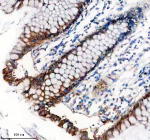

Applications of TNS4 antibody include western blotting, immunohistochemistry, and immunofluorescence. Western blot assays detect TNS4 protein in tumor cell lysates, immunohistochemistry maps expression in cancer biopsies, and immunofluorescence highlights localization at adhesion sites. These methods provide robust experimental approaches for studying cancer associated focal adhesion remodeling.